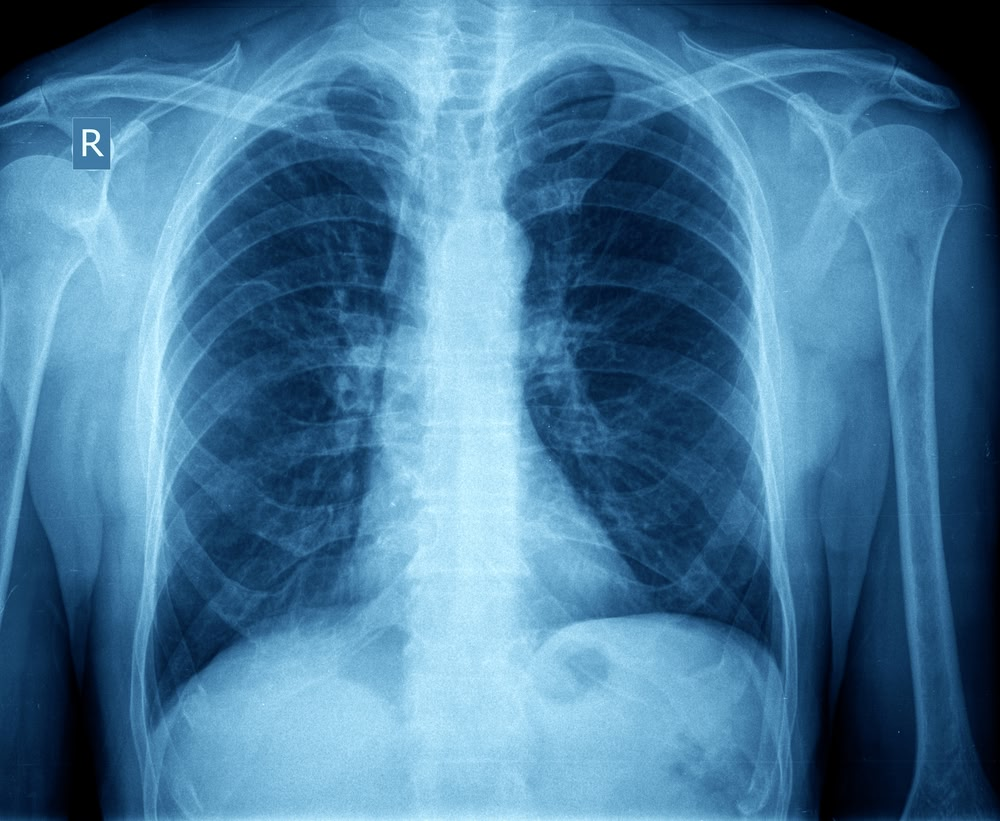

Золотым стандартом диагностики по клиническим рекомендациям является рентгенография органов грудной клетки. Отсутствие легочного рисунка, четкий край спавшейся анатомической структуры позволяет точно выставить диагноз. Определить тактику лечения.